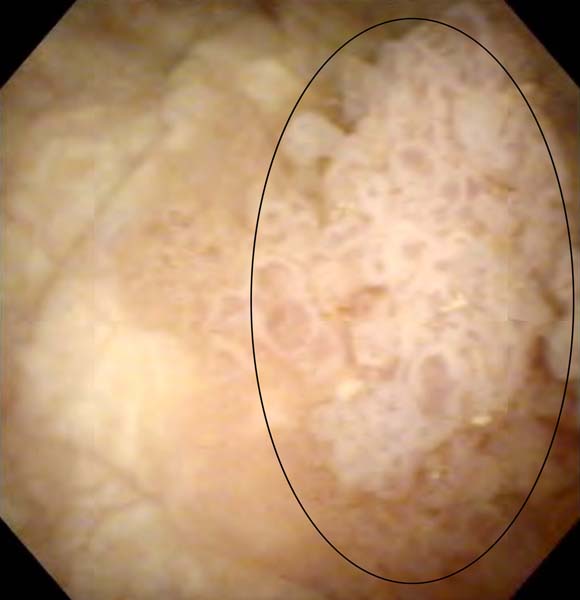

私自身がんに<1>膀胱の内視鏡画像を見たときのショック

疑いようのない画像結果に…(囲み部分)/(提供写真)